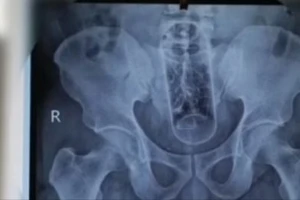

Dùng lọ nước yến thông hậu môn để trị… táo bón